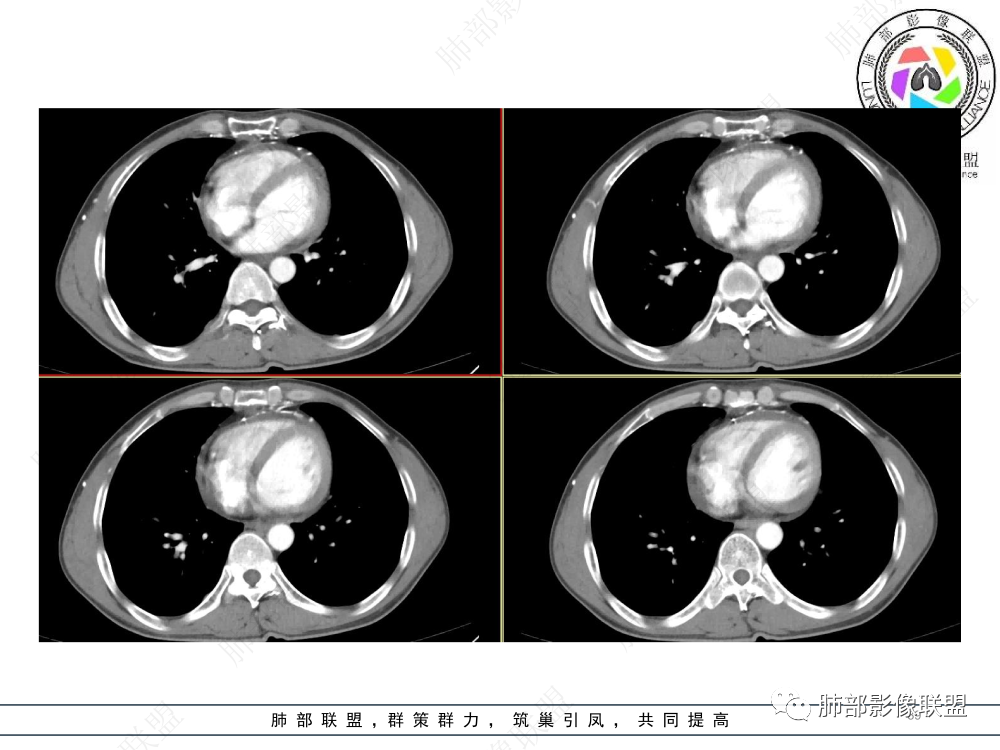

1.临床资料:中老年男性,病史较长-8个月,主诉胸痛,实验室资料:乳酸脱氢酶(LDH)升高。

2.影像表现:前上纵隔较大肿块,密度不均,形态不规则,边界不清,有结节样突起,脂肪间隙显示不清。病灶侵犯左无名静脉及上腔静脉,其中左无名静脉闭塞(胸背部侧支循环明显,亦表明回流受阻)。增强后轻中度不均强化。坏死边界欠清晰。可见心包积液,提示心包受侵犯。右侧上叶及纵隔胸膜下结节影,疑胸膜肺转移可能。胸骨柄后缘皮质不完整,疑骨质破坏(未提供骨窗及矢状位图像)。左锁骨上可见肿大淋巴结。

胸腺癌:病灶边界不清,骨骼及血管受侵破坏,胸膜、肺及心包受侵转移等首先想到胸腺癌。胸腺癌最常见病理类型为鳞癌,占70-79%。预后较差,50-65%初诊时伴肺转移,极少伴重症肌无力。影像:胸腺鳞癌形态不规则,易坏死,范围大,坏死区边缘常模糊。

胸腺瘤:胸腺瘤大多边界较清楚。边界模糊或心包侵犯可见于B3型胸腺瘤和癌,但胸腺瘤罕见远处转移、淋巴结转移和纵隔大血管侵犯。

淋巴瘤:体积常较大,常见常在10cm以上,相对低密度结节样堆砌感比较明显,对待骨骼、血管等结构相对“温和”,所谓“血管漂浮”、“肉包骨”则较为常见。病理类型几乎只见于:经典HD、大B细胞淋巴瘤,前驱T淋巴母细胞瘤。实验室检查LDH可升高。初诊时罕见钙化,罕见胸膜受侵。有坏死也常常边界清楚或呈囊变样外观,可伴纵隔、锁骨上淋巴结肿大。